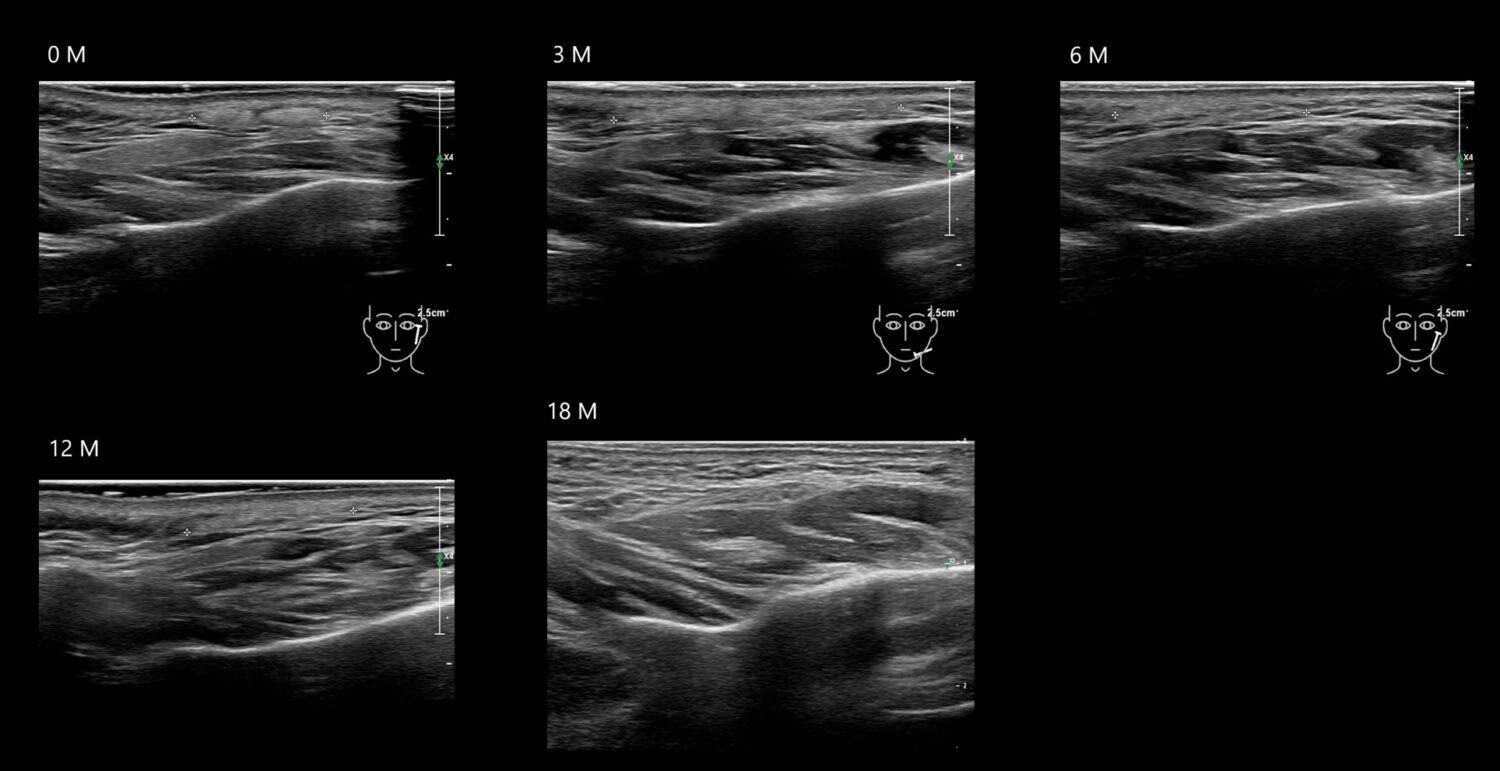

Fillers

Draw in the second image below where the fillers are located. To check if your answer is correct, swipe the first image to the right.